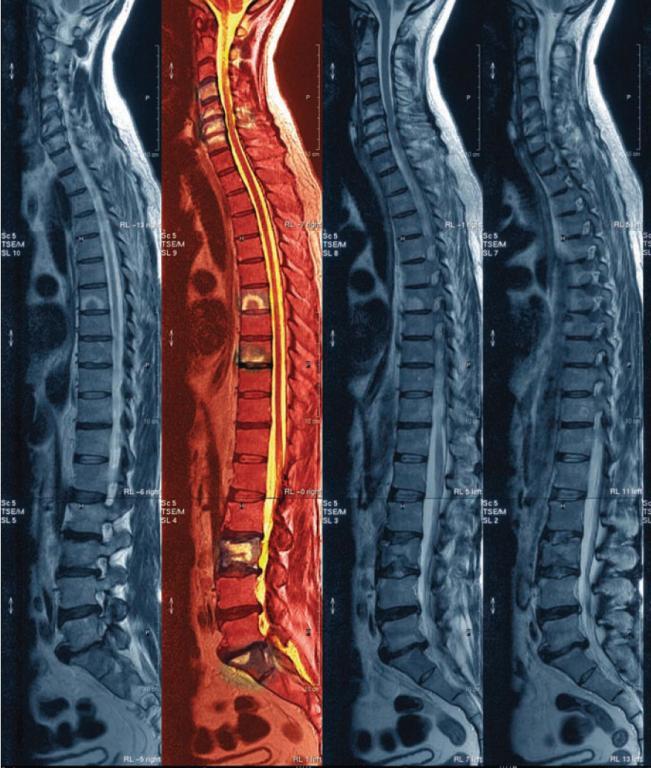

Esta visión cambia sustancialmente cuando se empiezan a introducir nuevas técnicas diagnosticas y terapéuticas fundamentadas en alta tecnología (endoscopia, radiografía, resonancia magnética, etc.) así como todo su soporte técnico para su uso e interpretación.